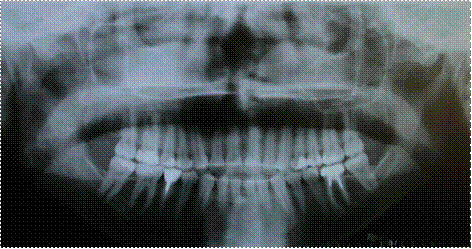

Результаты рентгенологических исследований пациентов в основной группе, по окончанию лечения, показали быструю оссификацию и возобновление плотности кости в участке перемещаемых резцов.

У 3 пациентов в контрольной группе процес оссификации происходил медленно, периодонтальная щель перемещённых резцов расширенная, плотность кости уменьшена.

Рис. 3.2.8. Фото отртопантомограммы больного «А», 29 лет, основная группа, после лечения.

Рис. 3.2.9. Фото отртопантомограммы больного «Б», 25 лет, контрольная группа, после лечения.